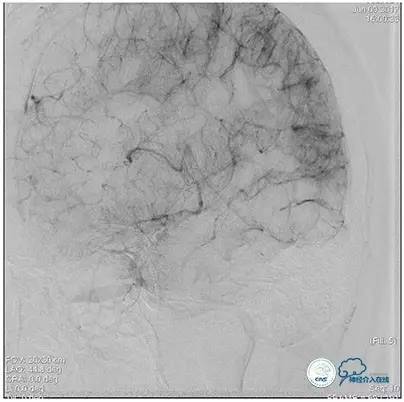

静脉淤滞

术中造影

术后造影

狭窄较前有改善